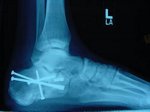

9. Dr.power

bueno,como q veo q no os ha gustado el barranquillo os pongo una foto para q os agais una idea de como tengo el pie.

Adjuntos:

Vaya mala suerte que has tenido macho, y encima a la ferretería de vez en cuando a por repuestos pal pié, siento mucho lo de tu caída, ya sé que no nos conocemos pero espero que te recuperes lo antes posible y te tíres por ahí la próxima vez detrás de Ribi y Paco R, que por lo visto te van a demostrar cómo se tira uno por esa "cuestecilla" y salir ileso, jeje.

Yo lo tengo facil ya que la cuestecilla la tengo cerca de casa :mrgreen: , ahora eso si me tirare con mi moutain bike, porque a dr.power se le fue la olla y lo provo con la flaca, y aqui tenemos la foto de las consecuencias :mrgreen: .